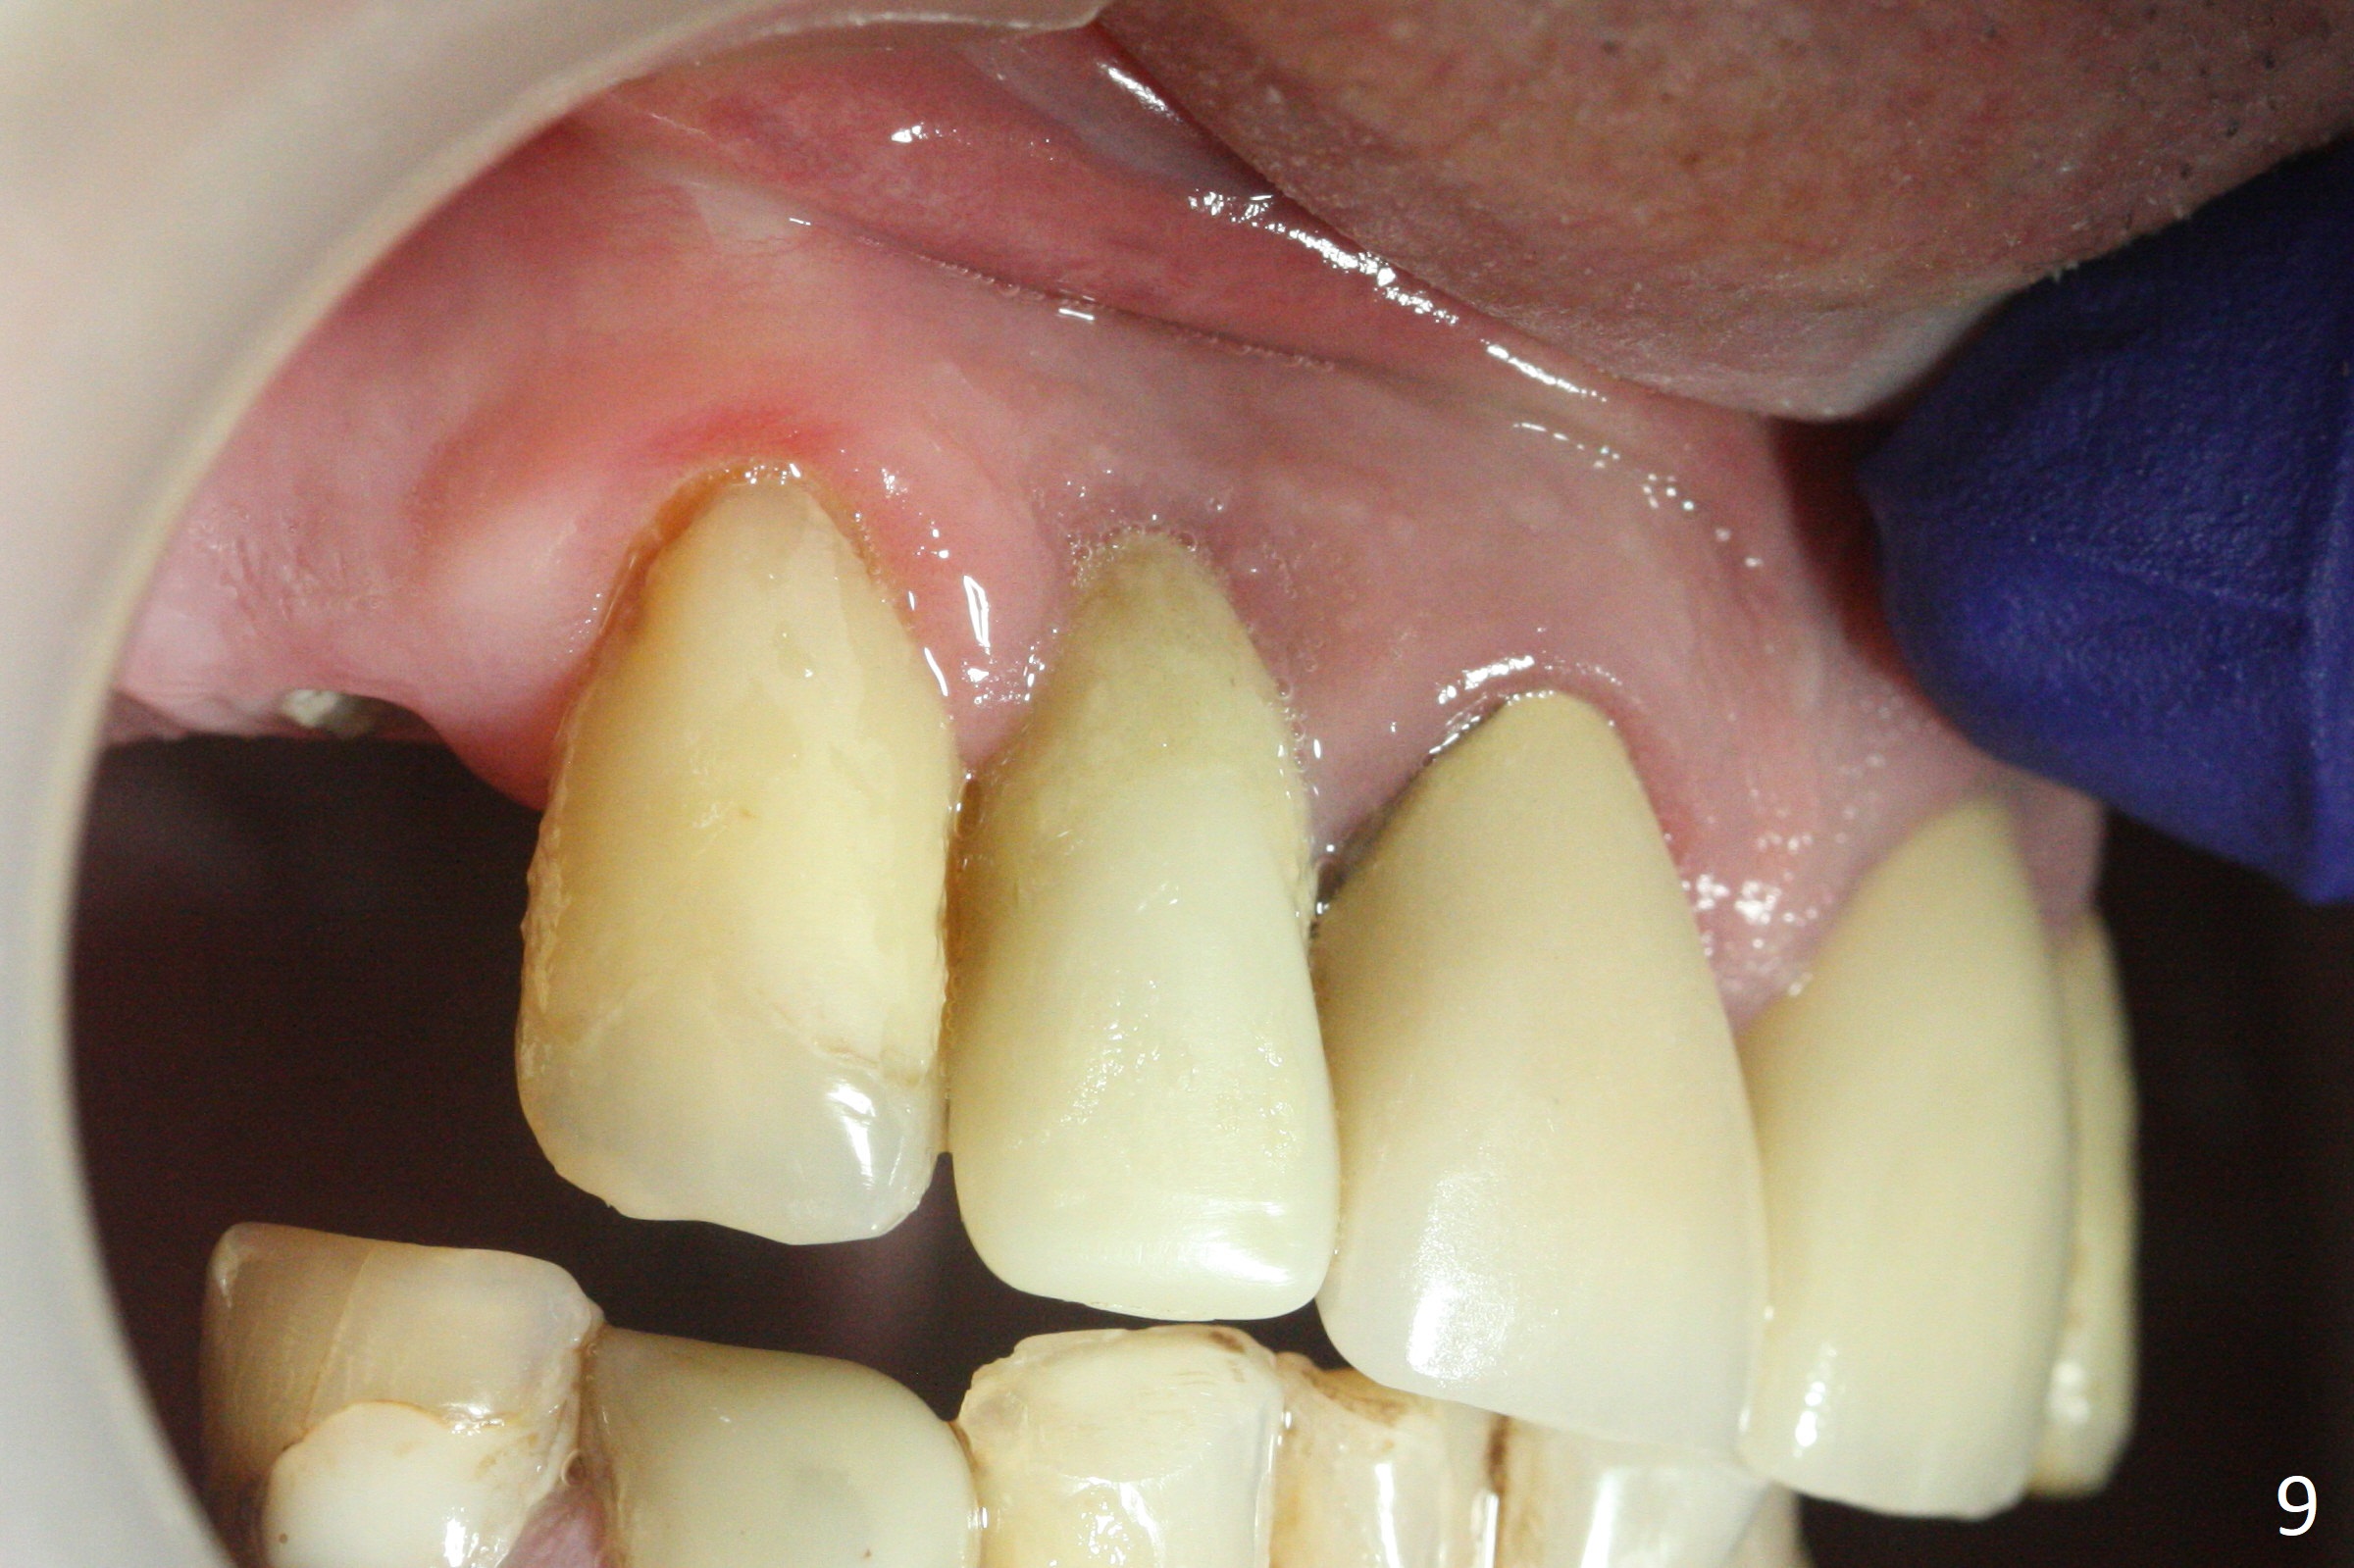

The gingiva adapts well to the provisional 1 week postop (Fig.8). The buccal gingiva remains recessive and the buccal plate is concave 5.5 months postop (Fig.9-11). It appears that the coronal portion of the buccal plate is resorbed 12 months postop (6 months post cementation, Fig.12 >). Socket shield or smaller diameter implant should have been done to avoid bone loss. Reanalysis of CBCT reveals that implantation apparently increases the bone width and that the buccal plate resorption is not so severe (Fig.13,14 (>: coronal end of the buccal plate)). Panoramic X-ray is taken 2 year 5 month post cementation.